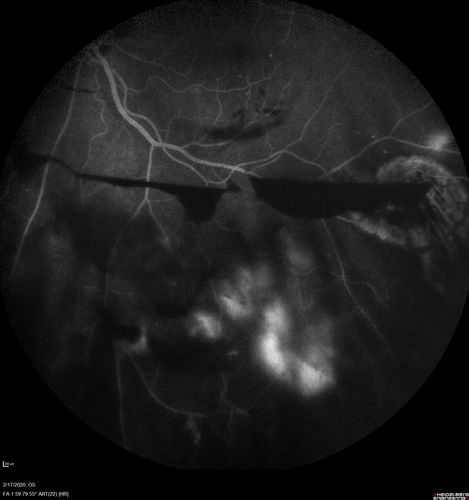

PDR and Vitreous Hemorrhage - High Risk Left Eye - Low Risk Right Eye

50 year old man with type I diabetes mellitus for 26 years. New Vitreous Hemorrhage in the left eye. Both eyes have NVE. Both also have foveal hypoplasia

Vitreous Hemorrhage and Proliferative Diabetic Retinopathy - Low risk right eye - High Risk Left Eye - Also Fovea Plana